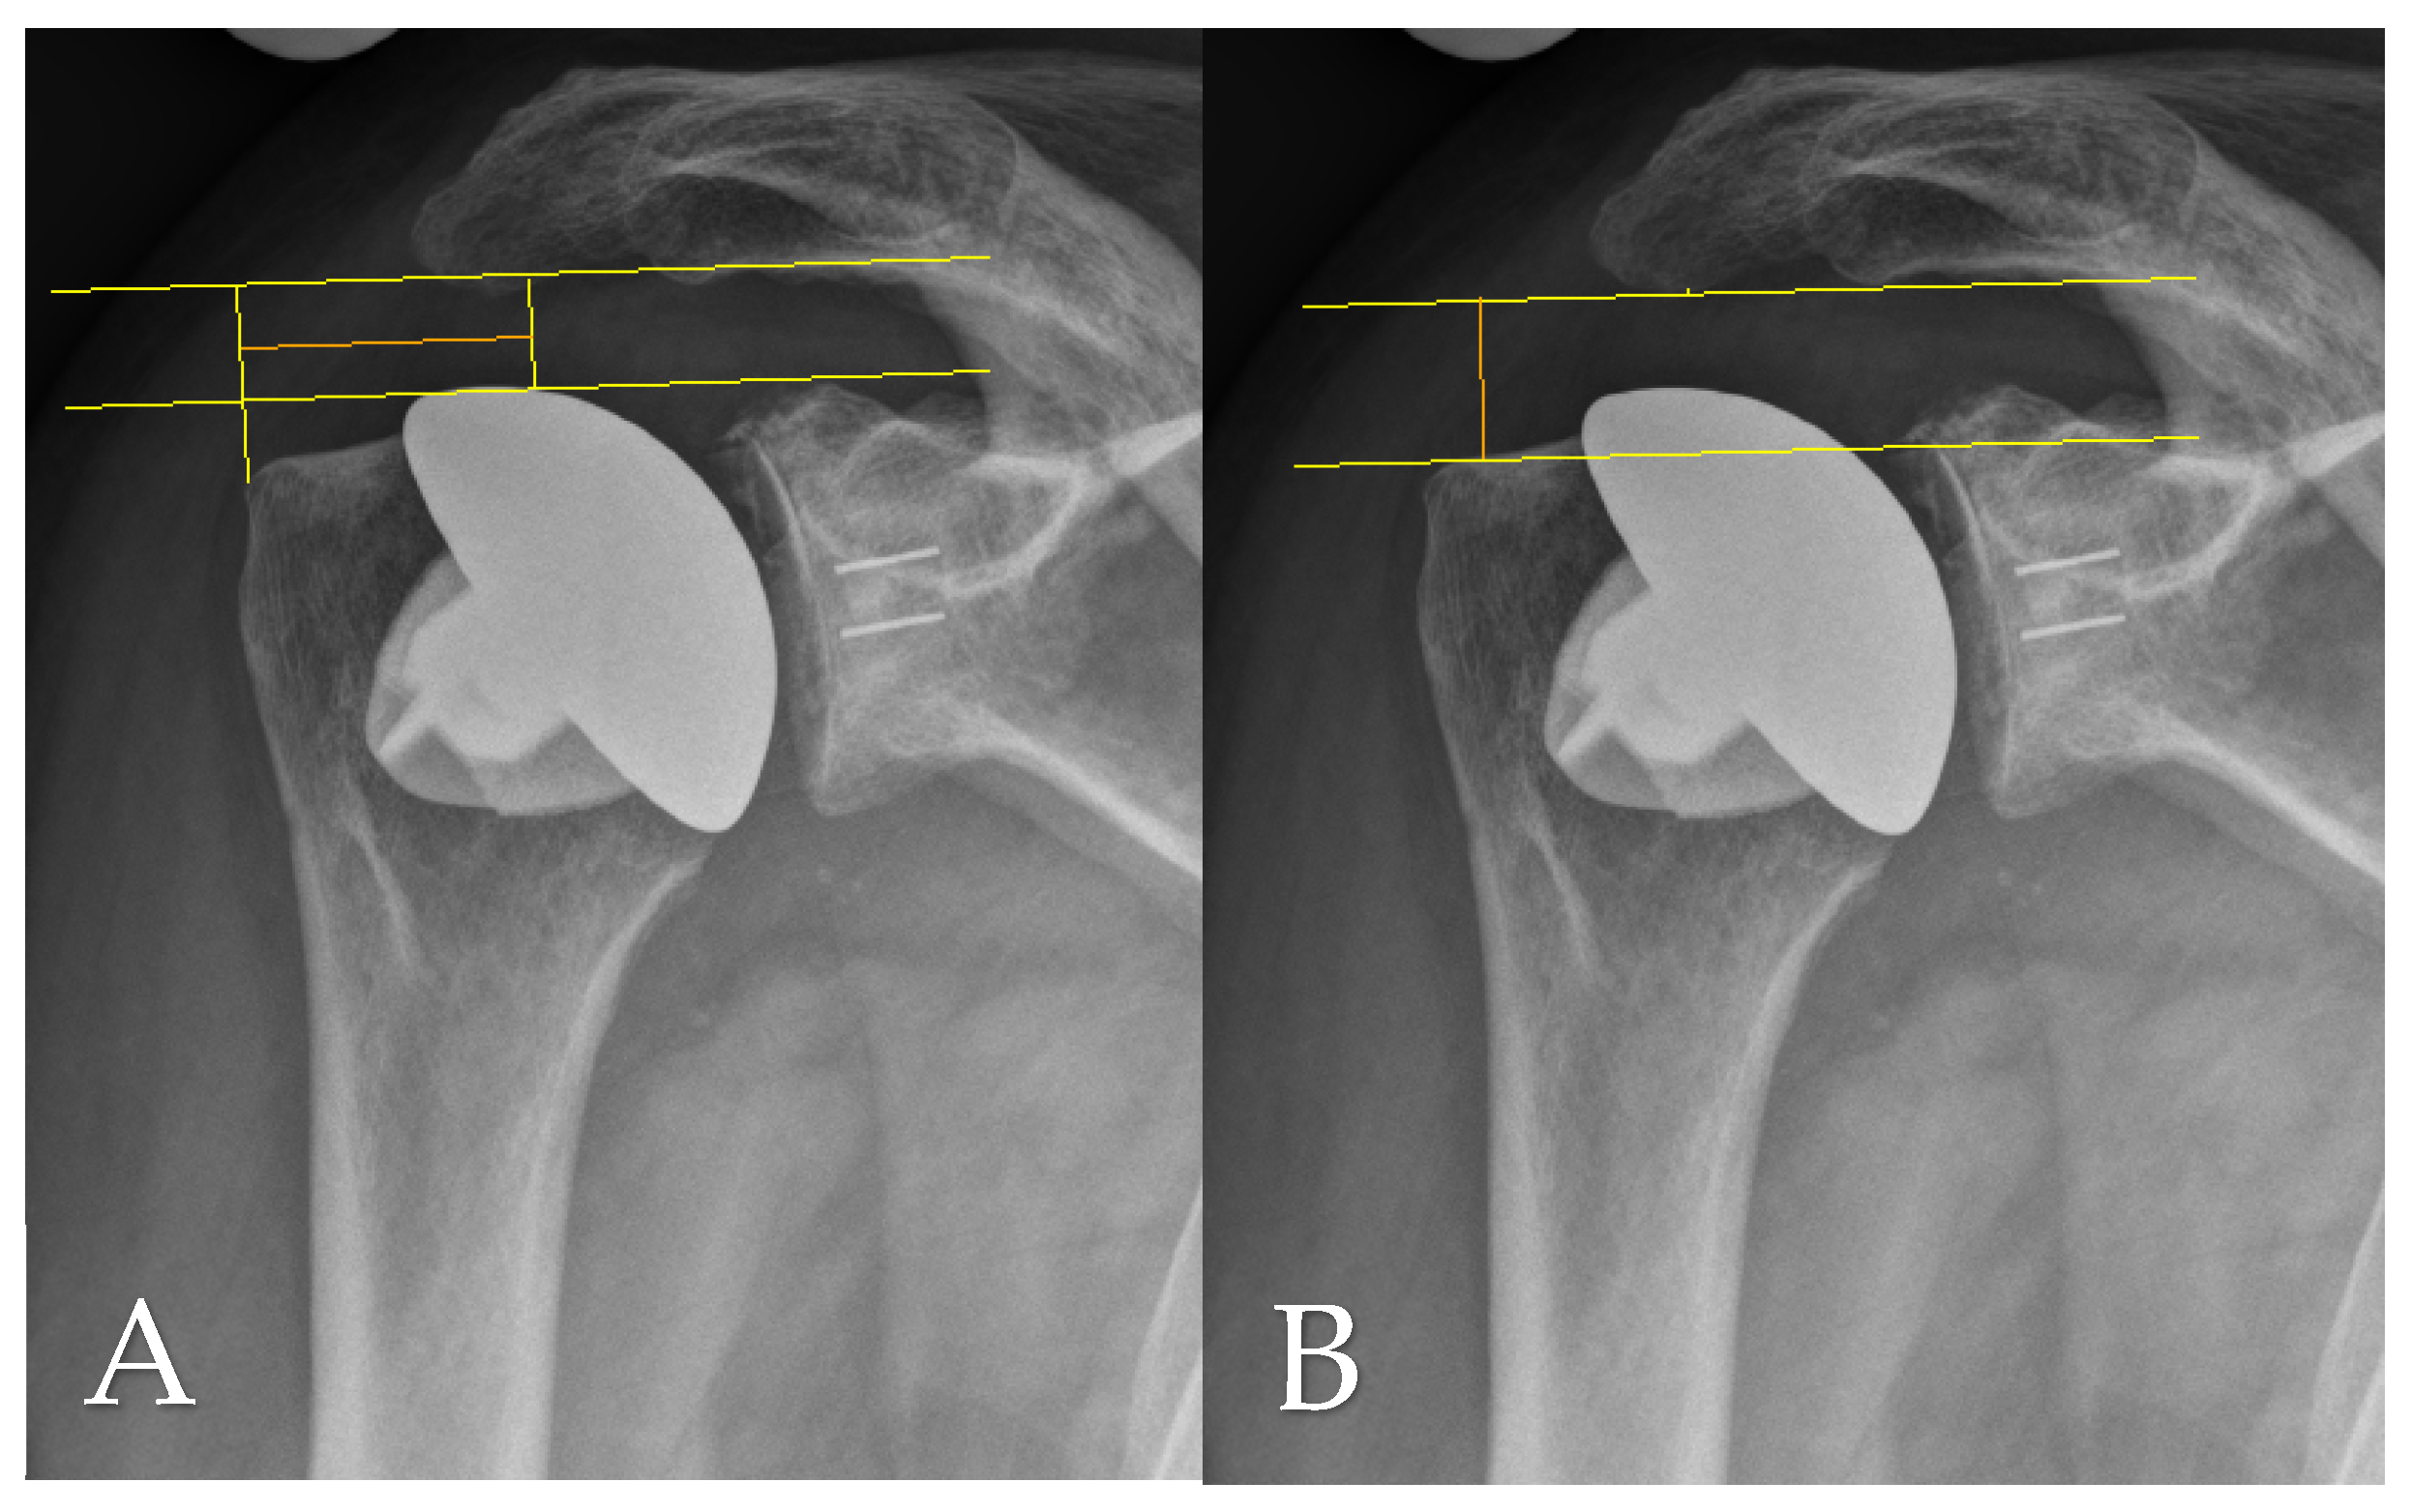

Radiographic evaluation at final follow-up was based on standardized anteroposterior and scapular Y-view radiographs, which were also consistently obtained during routine follow-up assessments. Postoperative imaging was used to analyze several anatomical and implant-related parameters, including the critical shoulder angle (CSA) as per Moor et al. [11], the acromiohumeral distance (AHD), lateral offset (LO), the head–stem index (HSI), and the extent of glenoid erosion following the classification systems proposed by Sirveaux [12], Lévigne, and Franceschi [13]. AHD was determined by measuring the vertical distance between the lateral aspect of the acromion’s undersurface and a horizontal line aligned with the upper border of the greater tuberosity, in accordance with the method described by Berthold et al. [14] (see Figure 1B). The CSA was calculated using lines drawn from the superior to inferior margins of the glenoid and from the inferior glenoid pole to the lateralmost point of the acromion, following Moor’s protocol [11] (Figure 2A). Lateral offset was assessed on true AP views by calculating the horizontal distance from the humeral head center to a vertical reference line extending from the lateral acromion margin to the humeral shaft (Figure 1A). The head–stem index (HSI) was computed as the ratio between the diameter of the humeral head and the shaft (stem) diameter, as outlined by Hochberger et al. [15] (Figure 2B). Assessment of glenoid erosion was conducted on AP radiographs and classified according to the established schemes of Sirveaux, Lévigne, and Franceschi, which consider both the magnitude of bone loss and the degree of medial displacement of the joint line relative to the scapular anatomy.

Figure 1. (A) Lateral offset (LO; orange line) and (B) acromiohumeral distance (AHD; orange line) measured on an anteroposterior radiograph at final follow-up.